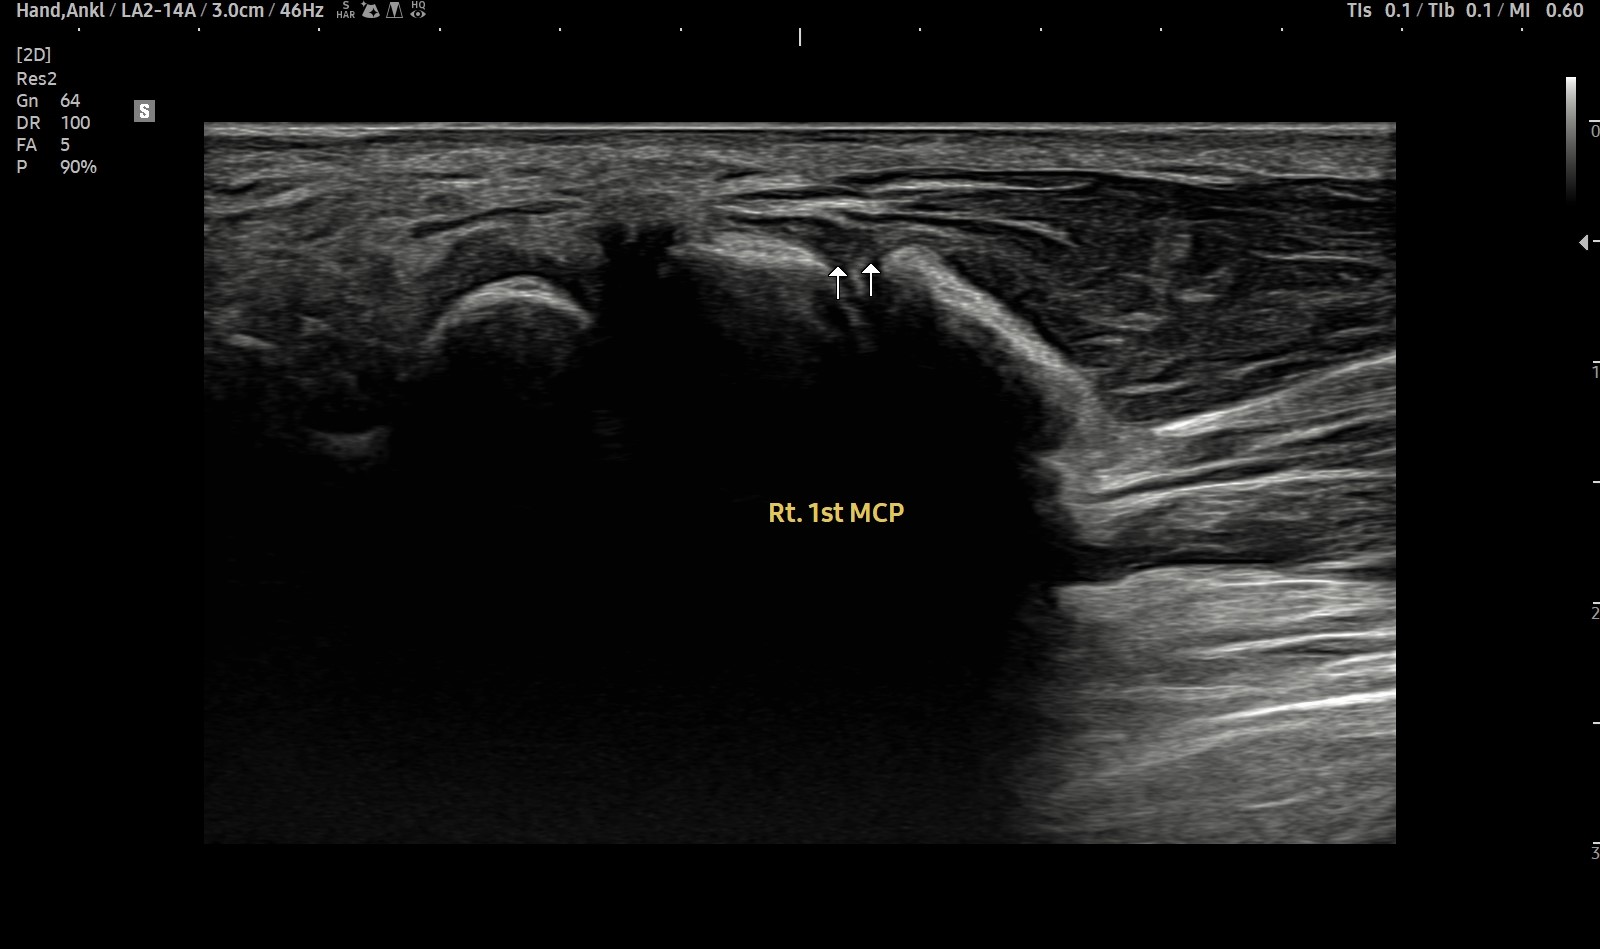

- 치료기간 : 25 . 6 . 9 ~ 25 . 10 .27

- 치료횟수 : 4 사이클(20) 회

치료전

치료 후

힘줄 두께 감소 및 전체적인 파열 부위 축소 & 골극 감소

-> 검사상 파열은 여전히 있지만 운동 이후에도 통증이 크게 없어서 치료 종료 후 3~4주정도 텀 두고 관찰 예정